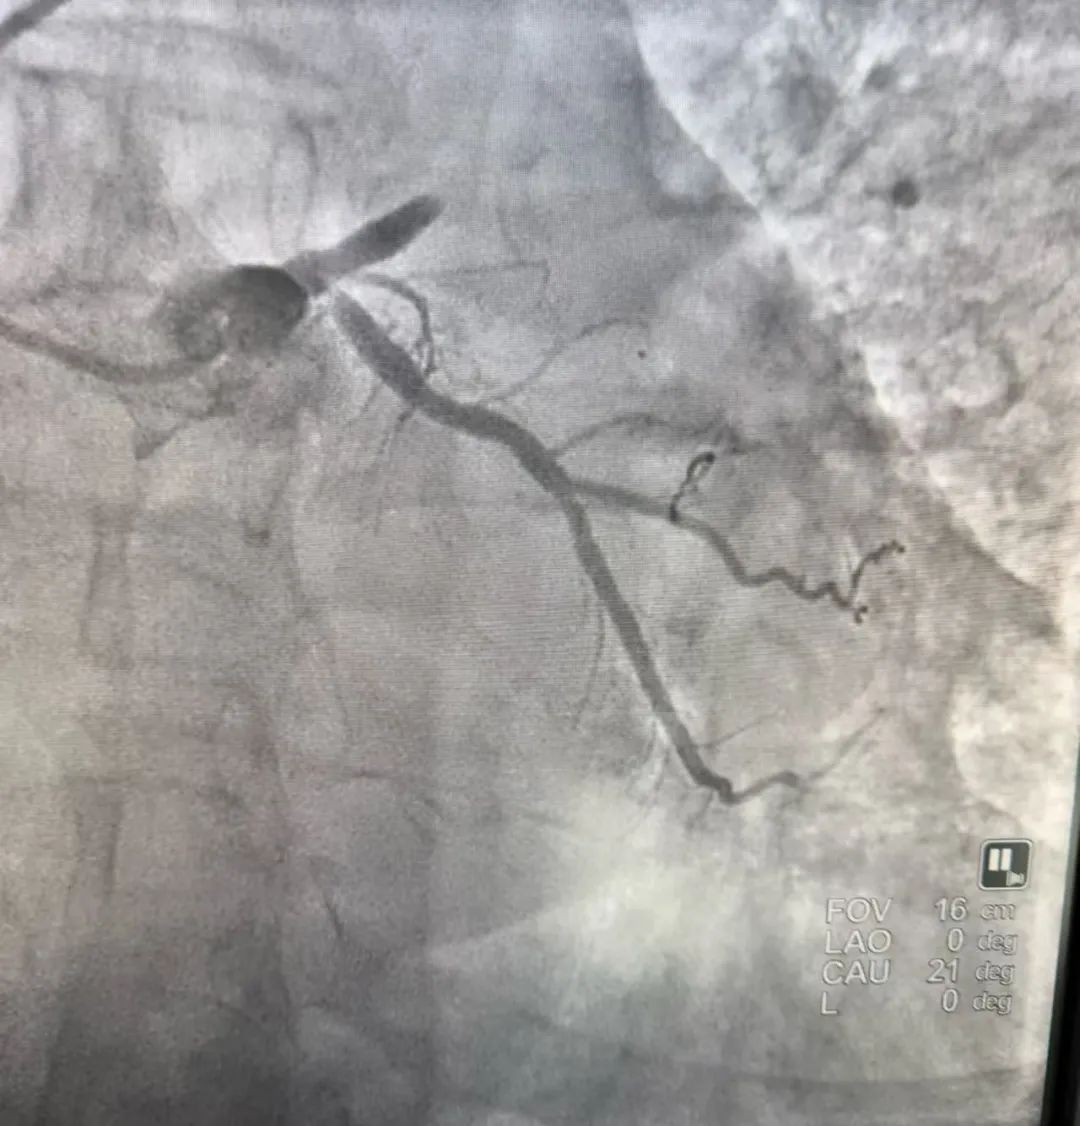

术前图

造影的结果正如我们预料的一样,前降支近端100%的闭塞。我们手术仅用时15分钟就快速地给病人开通了血管,植入了一枚支架。操作完成后,患者症状明显改善,心电图恢复正常,患者得救了。